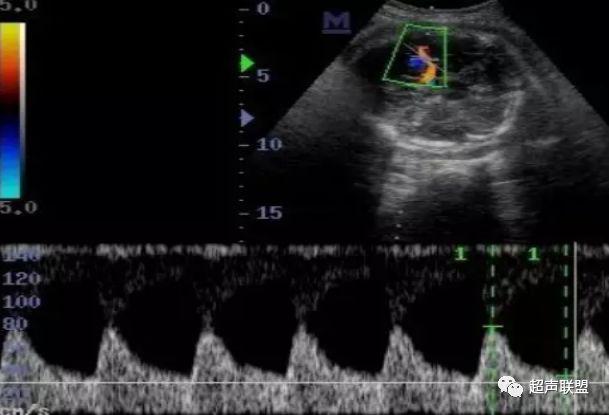

2 胎儿大脑中动脉测定

缺氧早期大脑血液供应增加,颅内血管扩张,阻力降低,舒张末期血流速度增加,PI、RI值降落,说明缺氧早期的血流再分配。当大脑中动脉RI、PI值明显降落,而脐动脉和腹主动脉的PI值升高,大脑中动脉PI值与脐动脉PI值的比值低于2个标准差时,提示严重缺氧的存在。

图3 正常大脑中动脉血流频谱

图4 大脑中动脉血流阻力减低